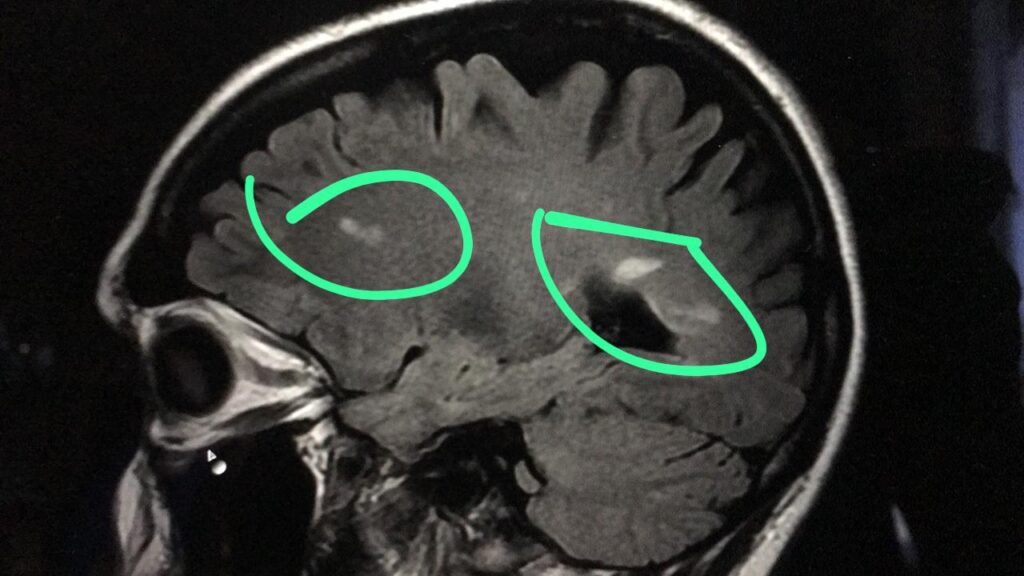

This case highlights the potential of modern experimental medicine in treating autoimmunity and neurodegeneration. Mee-Len was diagnosed with relapsing-remitting multiple sclerosis (RRMS) in 2018. In January 2023, she underwent cerebrovascular preconditioning and neurogenesis selective cellular transplant protocols. Over the following year, she experienced significant improvement in her symptoms and a halt in disease progression, as confirmed by brain imaging.

Initially, she had a symptom classification of Expanded Disability Status Scale (EDSS) 2.5 at baseline, with considerable brain lesion volume. By January 2024, her EDSS score improved to 0. Brain and spine contrast MRI scans conducted between the baseline and January 2024 showed no further progression of her RRMS. As of now, two years later, Mee-Len remains symptom-free and medication-free, living her life to the fullest.